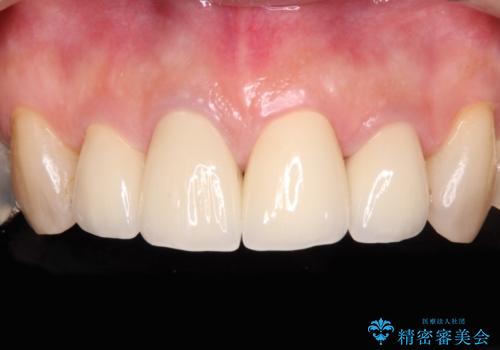

痛む奥歯と見栄えの悪い前歯 オールセラミックによる補綴治療